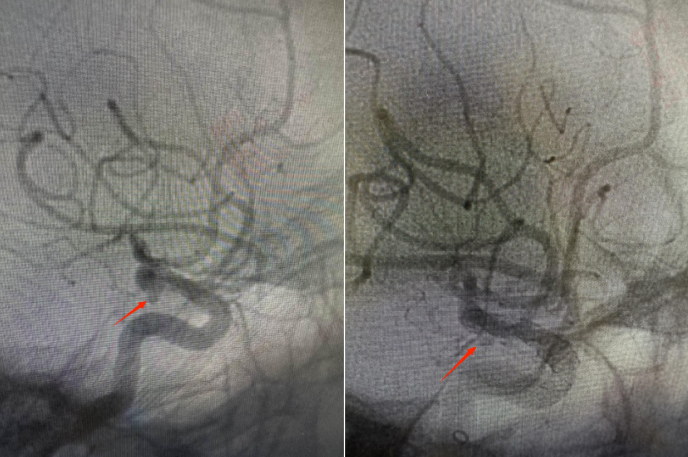

术后造影显示,动脉瘤开口被完全覆盖,支架贴壁良好,动脉瘤内造影剂明显滞留,瘤体附近穿支动脉保留完好,载瘤动脉血流通畅,手术取得圆满成功。患者术后第二天正常下地活动,第三天顺利出院。

△术前动脉瘤形态,术后瘤体内造影剂延时显影并滞留